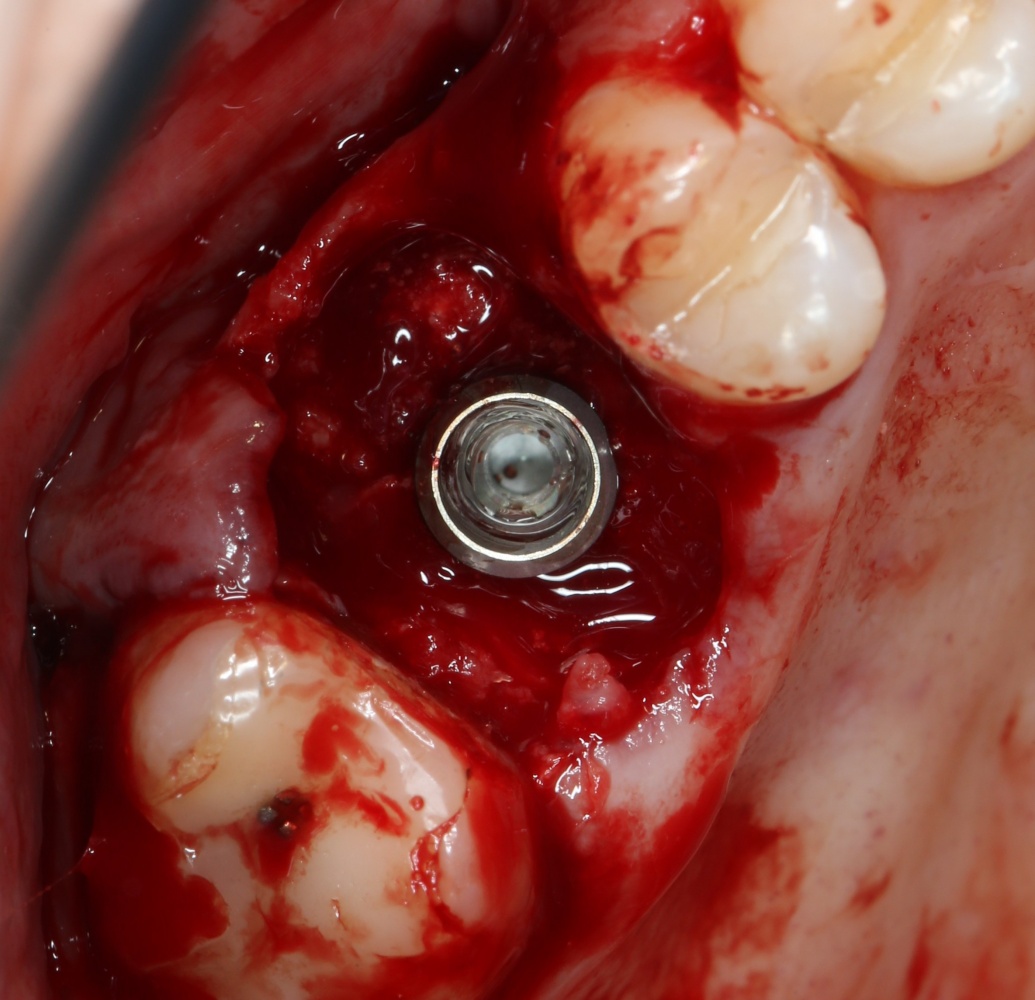

Все начинается с удаления зуба:

Обратите внимание на состояние вестибулярной стенки лунки. В проекции верхушек корней вы можете увидеть костный дефект, вызванный длительным воспалительным процессом (собственно, почему этот зуб пришлось удалять). В этом случае, вестибулярная стенка лунки неизбежно лизируется после удаления зуба, а это приведет не только к проблемам в эстетике, но и осложнит последующий уход за протетической конструкцией. Поэтому в данном случае мы должны продумать, в том числе, аугментацию лунки. И порядок действий здесь несколько иной, нежели в предыдущем случае.

Устанавливается имплантат Astratech (Dentsply Implants):

Для аугментации также используем Bio-Oss Collagen 100 mg, нарезаем его по размеру с помощью скальпеля и позиционируем в лунках щечных корней:

На имплантат ставим формирователь, ушиваем лунку. Напомню, что любой биоматериал должен быть герметично запечатан в ране (фактор успеха III). В противном случае, от него больше вреда, чем пользы: